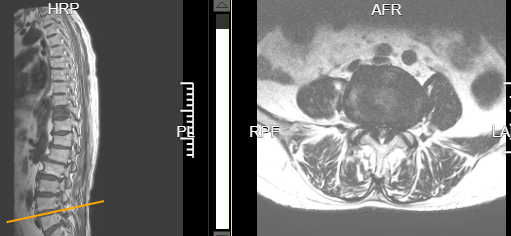

术前腰4/5椎间盘突出并椎管狭窄